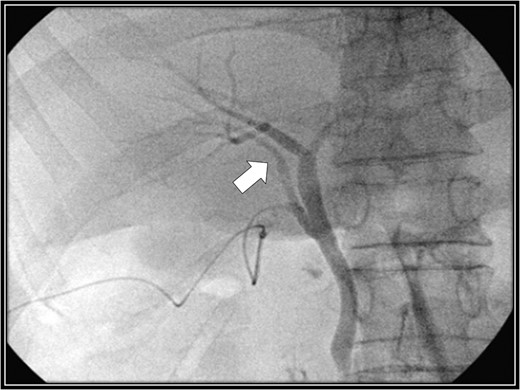

Intraoperative cholangiography image. The right accessory hepatic duct branching from the cystic duct (white arrow) dominates an anterior segment of the right hepatic lobe.

The patient was placed in supine position. Initially, intracorporeal procedures were performed in the laparoscopic view through four trocars (one 12-mm port and three 5-mm ports). We considered using intraoperative cholangiography to explore the right accessory hepatic duct. We incised the serosa by the neck of the gallbladder, used the Rouviere sulcus as a landmark, and peeled off the Calot triangle near the gallbladder. Subsequently, we identified the cystic artery and isolated it. Then we identified the cystic duct, and we inserted a cholangiography tube into it. The intraoperative cholangiography image showed that the right accessory hepatic duct branching from the cystic duct dominated an anterior segment of the right hepatic lobe (Fig. 3). Next, we isolated the cystic duct while preserving the right accessory hepatic duct. We resected the gallbladder. The total operating time was 125 min, and the intraoperative blood loss was minimal. Since the patient's postoperative course was uneventful, he was discharged 4 days later. We performed drip-infusion cholangiography-CT (DIC-CT) 48 days postoperatively. The DIC-CT scan demonstrated that the right accessory hepatic duct was intact, and it dominated an anterior segment of the right hepatic lobe (Fig. 4).